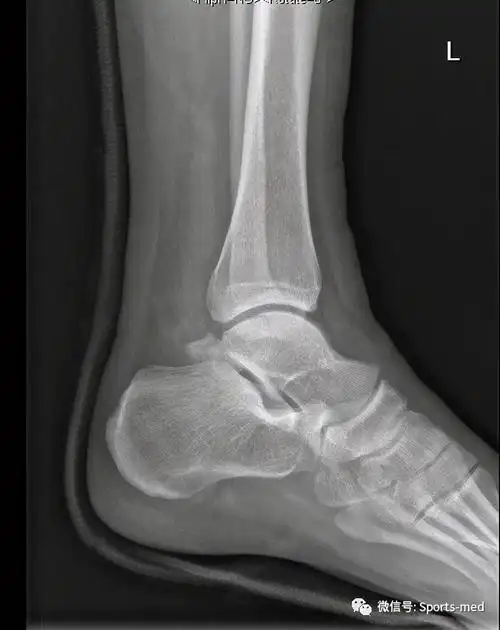

黄石市第二医院赵玉兴-踝关节侧位.jpg

x射线踝关节.

踝关节x线片或右踝关节ap和侧位片诊断踝关节骨折.